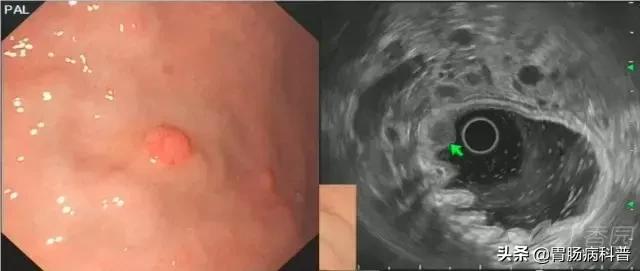

图4 异位胰腺(浅型)。

白光胃角可见脐样黏膜下隆起,超声内镜下可见黏膜肌层-黏膜下层有一界线不清之偏高回声病变